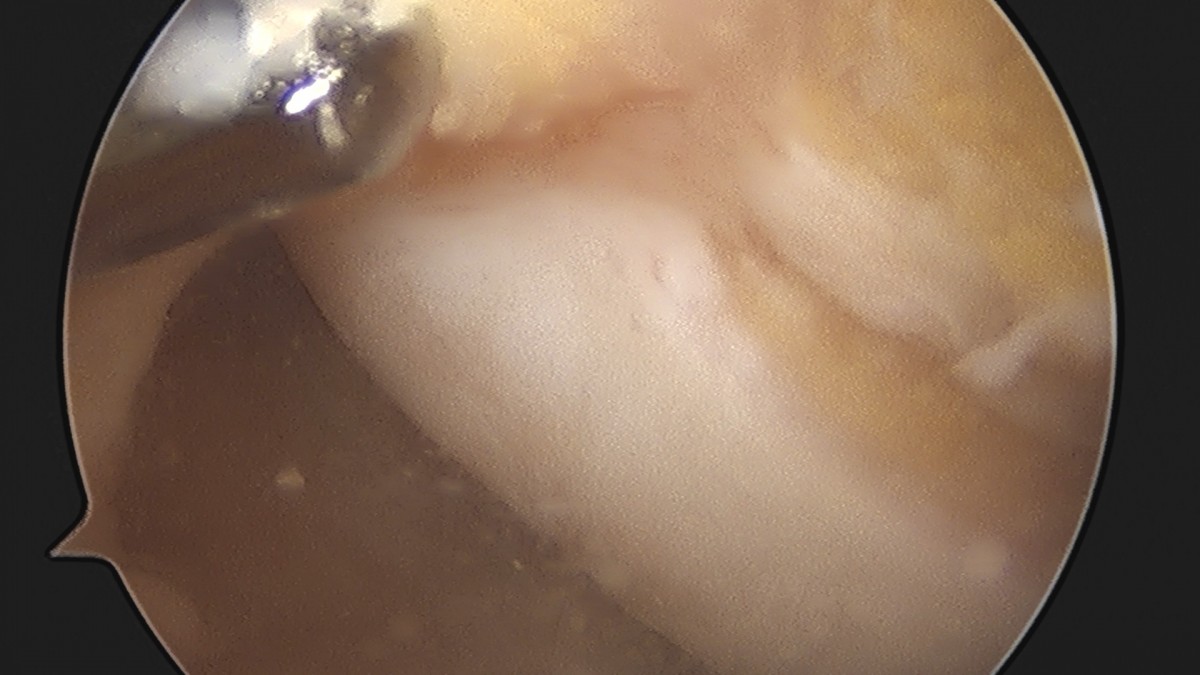

이재상원장님 무릎 반월상 연골판 절제술 박상O 환자

dae765e4d9ac96aee867c9d6292d8784_1758006444_8198.jpg